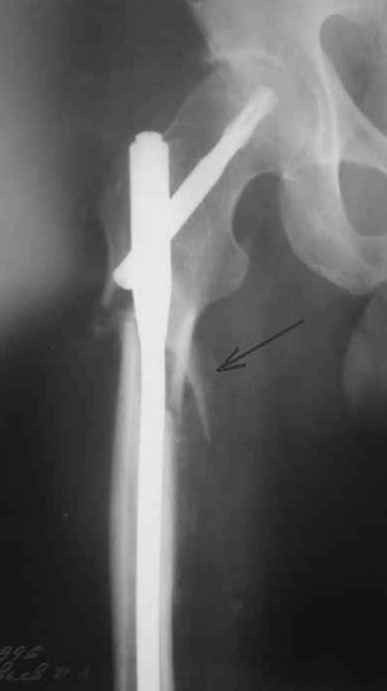

Alexander Chelnokov> Практически единственное, что делает необходимым разрез для манипуляций с промежуточным отломком бедренной кости - это его "застегивание" в илиотибиальном тракте по типу пуговицы в петле.

На операции я оставил осколок в области приводящих мышц бедра (ни пальпаторно, ни спицей сдвинуть не смог, "заклинило" насмерть). Фото спустя 2 месяца после операции (PFN).

Только сейчас пациент стал более или менее активным. Сразу после операции жалобы на сильные боли при отведении и приведении бедра в области отломка. Сейчас отломок пальпируется и пациент испытывает дискомфорт, хотя амплитуда движений объективно прогрессирует.

Теперь думаю, надо все-таки было через минидоступ или резецировать, либо репонировать. Обычно при таких операциях уже на 2-й день пациенты на костыли и по отделению, а у этого задержка длительная получилась. Только спустя 2 недели кое-как на костыли взобрался. Ни отека, никакой неврологии, только эти боли в области осколка.